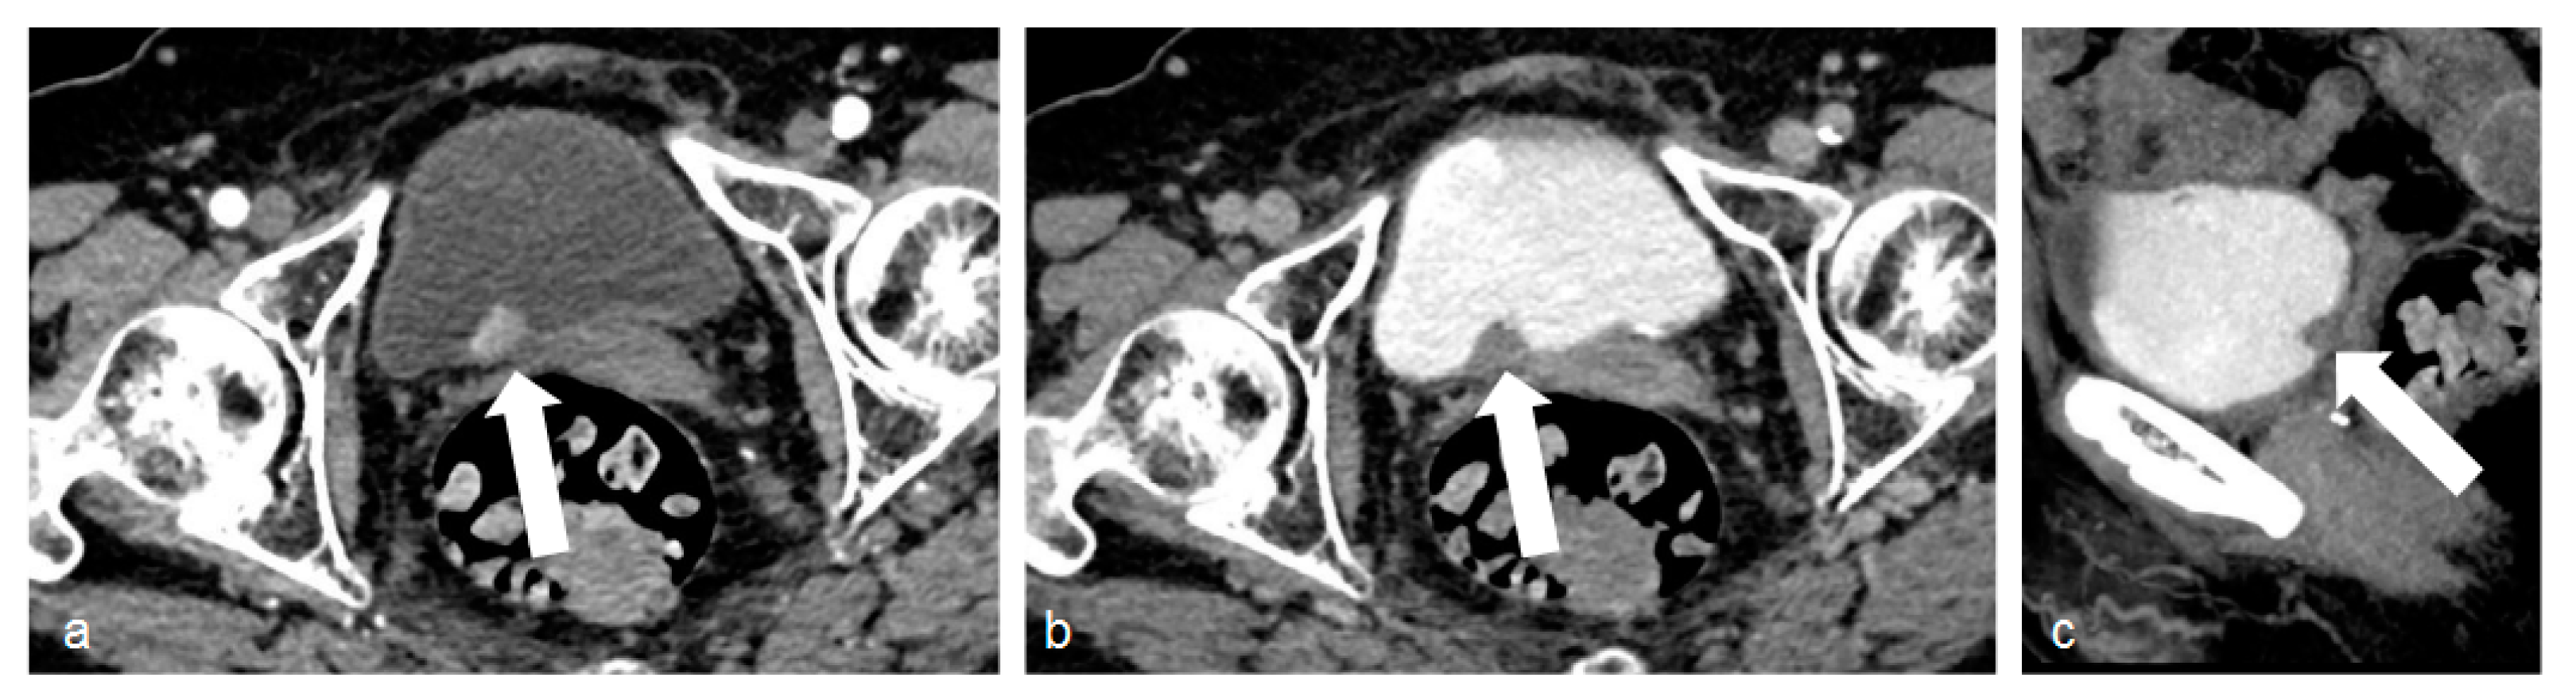

Figure 1.

Images of bladder cancer. (a) The corticomedullary phase acquisition with a polypoid lesion originating from the posterior bladder wall, characterized by high contrast enhancement (white arrow). In the excretory phase (b) and its sagittal reconstruction (c), the lesion is clearly visible as a filling defect in the iodinated urine-filled bladder (white arrows).